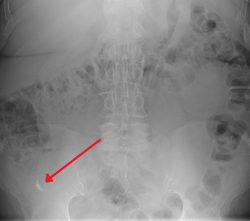

In general, plain abdominal radiography (PAR) is not useful in making the diagnosis of appendicitis and should not be routinely obtained from a person being evaluated for appendicitis.[65][66] Plain abdominal films may be useful for the detection of ureteral calculi, small bowel obstruction, or perforated ulcer, but these conditions are rarely confused with appendicitis.[67] An opaque fecalith can be identified in the right lower quadrant in fewer than 5% of people being evaluated for appendicitis.[45] A barium enema has proven to be a poor diagnostic tool for appendicitis. While failure of the appendix to fill during a barium enema has been associated with appendicitis, up to 20% of normal appendices do not fill.[67]